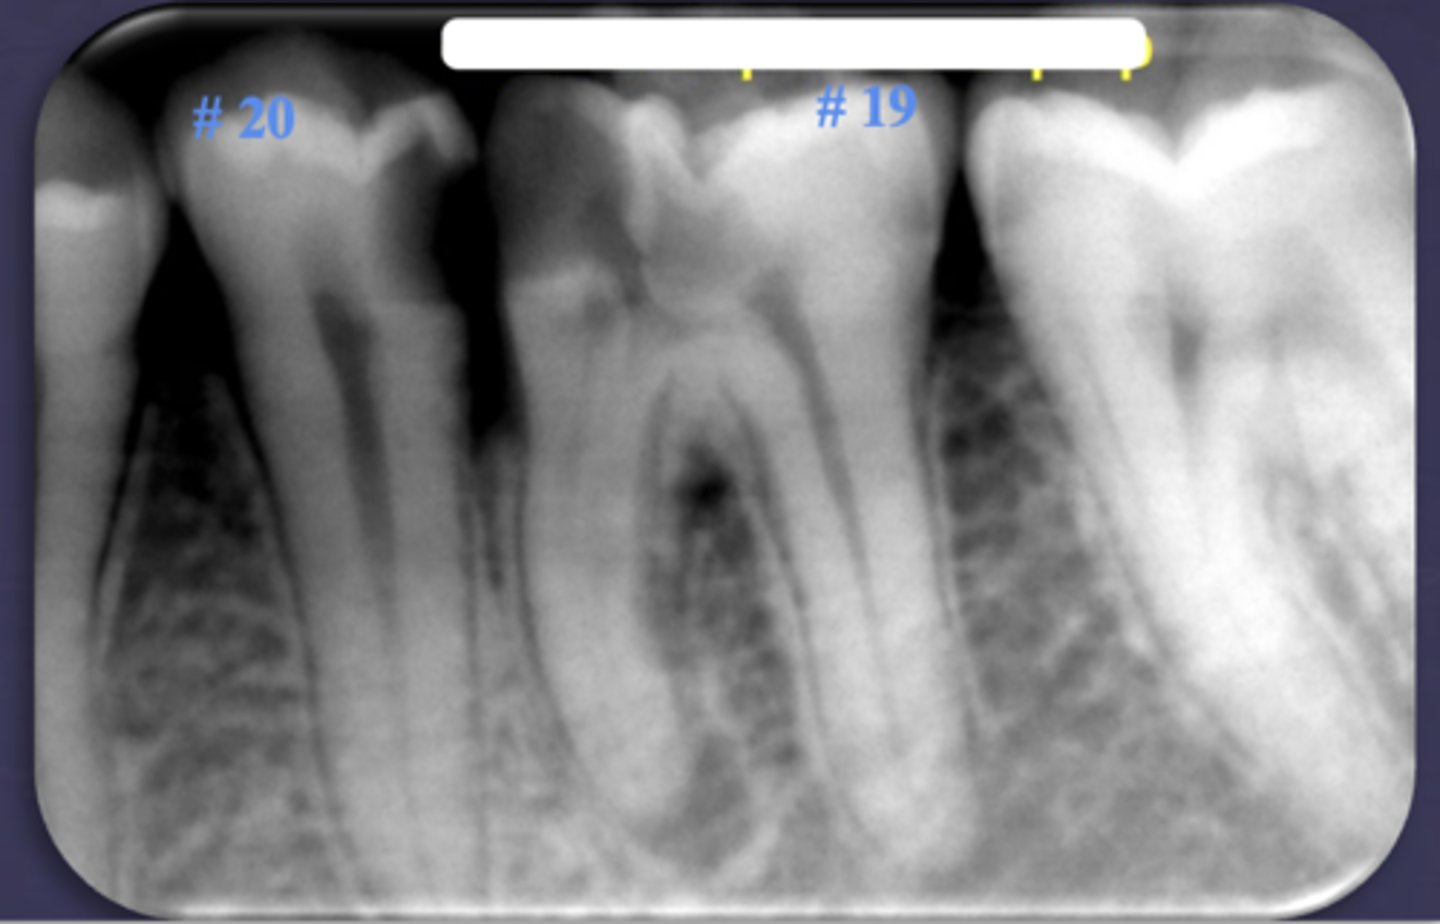

What are two defects that the arrows are pointing to?

- Widened PDL

- Sclerosis

What type of change is seen in this radiograph?

early change (apical periodontitis #30)